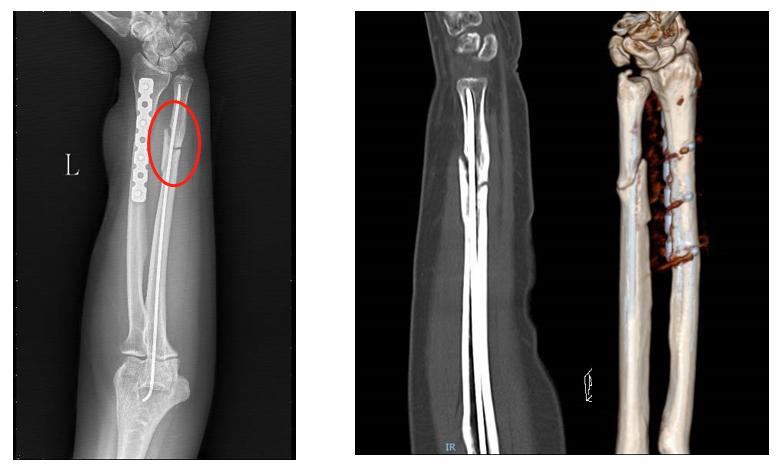

下面给大家介绍一个比较经典的病例,这是一个女性患者,由于机器挤压,导致导致前臂的尺骨和桡骨出现了双骨折,由于局部的皮肤剥脱比较严重,因此选择了钢板固定桡骨,尺骨选择闭合复位的弹性钉固定的治疗方案。

(初次受伤X线片)

(清除坏死皮肤,桡骨钢板内固定,尺骨闭合复位弹性钉内固定,皮瓣修复创面)

但很不幸的是,病人在手术后6个月和9个月复查的时候拍片发现尺骨的骨折间隙非常明显,骨头没有长到一起,这在骨不连的分类上属于传统意义上的扭转楔形骨不连。传统观念认为这种类型骨不连局部的生物活性是非常差的,所以只能选择植骨的手术方式。

(术后6个月)

(术后9个月)